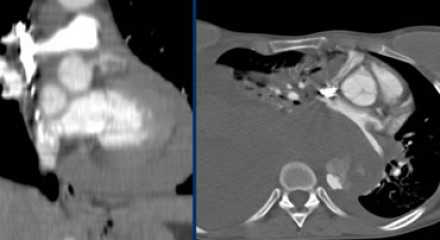

- Ниже представлены исследования пациента в разница в 2 года.

- Гемиперикард, гемомедиастенум и гемиторакс являются грозными осложнениями диссекции аорты.

- Ниже представлен пациент с полным тромбированием ложного просвета. Спустя 5 дней после первого обращения пациент жалуется на резкую боль в груди, а снимках визуализируется кровоток в ложном просвете.

- Увы, но пациентка не могла продолжить лечение хирургически по разным причинам, поэтому лечилась медикаментозно.

- Порой сложно дифференцировать тромбированный просвет при диссекции и аневризму с тромбом.

- Если интима кальцинированна, то это очень помогает.Слева — тромбированный просвет при диссекции. Справа — аневризма с тромбом на внутренней стороне кальцинированной интимы.